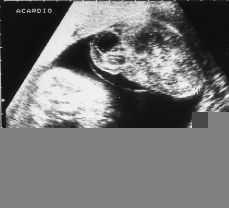

En la semana 28,6 el feto sano sigue creciendo adecuadamente, objetivándose ya un polihidramnios moderado, mientras que el feto acardio ha aumentado de tamaño, midiendo en estos momentos 88-64 milímetros sin objetivarse edema como suele ser frecuente cuando existe un trastorno hemodinámico fetoplacentario (Fig. 2).

Figura 2.Ecografía prenatal por vía vaginal. El feto acardio mide 110 por 88 mm. Se independiza en sus inmediaciones una fina banda hiperecogénica que representa un amnios separando al feto acardio de la bolsa del otro gemelo.